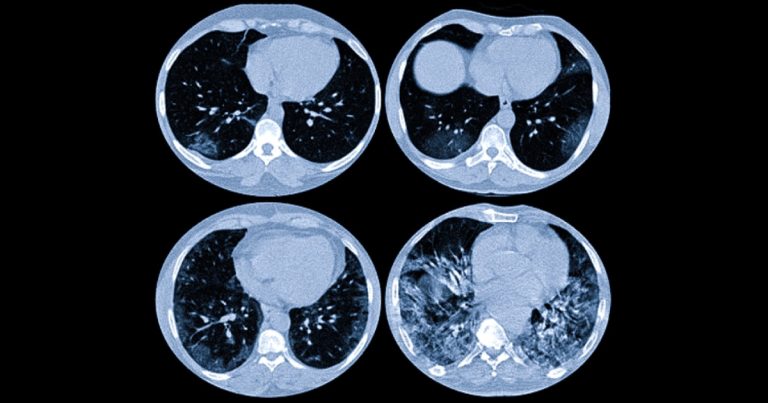

Лімфоми та саркоїдоз: як змінюються лімфовузли грудної клітки

Статті Автор: Alla Kovshova

Коли під час обстеження грудної клітки лікар каже про «збільшені лімфовузли», це завжди викликає тривогу. Проте причини таких змін можуть бути дуже різними: від системного запалення…

Променеве навантаження: скільки разів на рік можна робити КТ?

Комп’ютерна томографія (КТ) — один із найінформативніших методів діагностики. Вона допомагає швидко виявити травми, пухлини, запальні процеси та багато інших станів. Але разом із цим пацієнтів…

Онкоскринінг «Total Body»: чи можна побачити все тіло за одне обстеження?

Сучасна медицина рухається у напрямку максимально раннього виявлення онкологічних захворювань. Чим раніше знайдена пухлина — тим вищі шанси на ефективне лікування та повне одужання. На цьому…